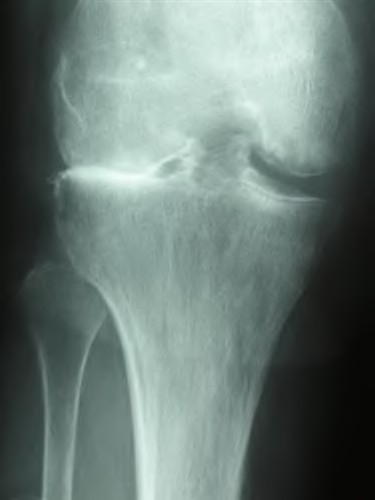

Question 13:

A 32-year-old woman complains of left knee pain. Radiographs show an eccentric, purely lytic lesion in the distal femoral epiphysis extending to the subchondral bone, without a sclerotic margin. Biopsy reveals multinucleated giant cells interspersed among mononuclear stromal cells. For recurrent or surgically unsalvageable cases of this specific tumor, which of the following is the most appropriate targeted medical therapy?

Correct Answer: Denosumab

Explanation:

This is a Giant Cell Tumor (GCT) of bone. The neoplastic cells in GCT are actually the mononuclear stromal cells, which heavily express RANKL (Receptor Activator of Nuclear factor Kappa-B Ligand). This expression recruits and activates normal osteoclasts (the giant cells), causing massive osteolysis. Denosumab, a monoclonal antibody against RANKL, is the medical treatment of choice for unresectable or highly recurrent GCTs.